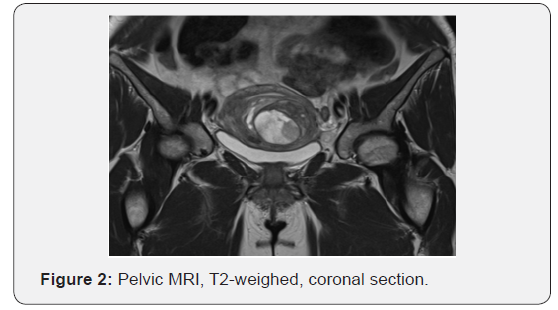

The medical history should include an assessment of risk factors associated with uterine sarcoma. Clinical examination may reveal an enlarged uterus. Serum tumor markers (CA-125 and lactate dehydrogenase) have been reported to be elevated in uterine sarcoma but they are not diagnostic [10]. Preoperative imaging cannot reliably differentiate between benign fibromas and uterine sarcomas. Suspicious ultrasound findings may include multiseptated cystic areas and multiple small areas of cystic degeneration [11]. On magnetic resonance imaging LGESS may appear as a polypoid endometrial mass with low signal on T1-weighted images and heterogeneously increased high T2 signal. Myometrial and lymph vascular invasion can be noted. Contrast enhancement is moderate and often heterogeneous [12]. However these findings cannot set the definite diagnosis of malignancy.

A 43-year-old parous patient presented to our Gynecology Clinic for surgical management of uterine leiomyomas causing menometrorrhagia. Ultrasound examination revealed two leiomyomas. Furthermore, following MRI depiction revealed more than three leiomyomas, the largest being 6 x 4.5 cm in dimensions. (Figures 1 & 2) The patient’s medical and surgical history was insignificant and the tumor markers were negative. Pap smear free for malignancy. After preoperative assessment the patient was led to surgery where she underwent a subtotal abdominal hysterectomy without salpingooopherectomy (as it was her preference to preserve the cervix and the adnexae).